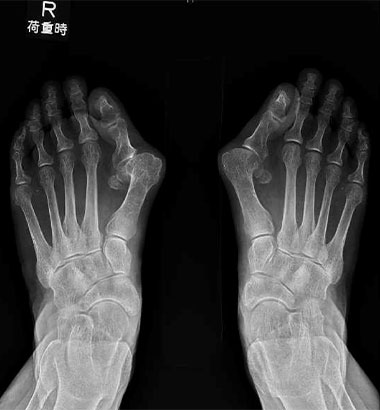

外反母趾やあしゆびの変形に対しては、変形の程度、痛みの強さ、関節の状態、生活スタイルなどを総合的に判断し、患者さん一人ひとりに最適な術式を選択します。

骨幹部骨切り術 (Mann変法):

あしのおやゆびの骨(第1中足骨)を切り、おやゆびの角度を調整し、変形を矯正する方法です。

術前

術後